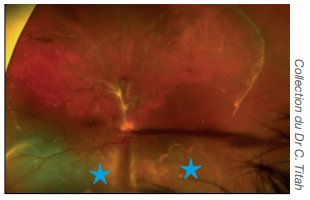

Décollement de rétine

Engainement blanchâtre des vaisseaux